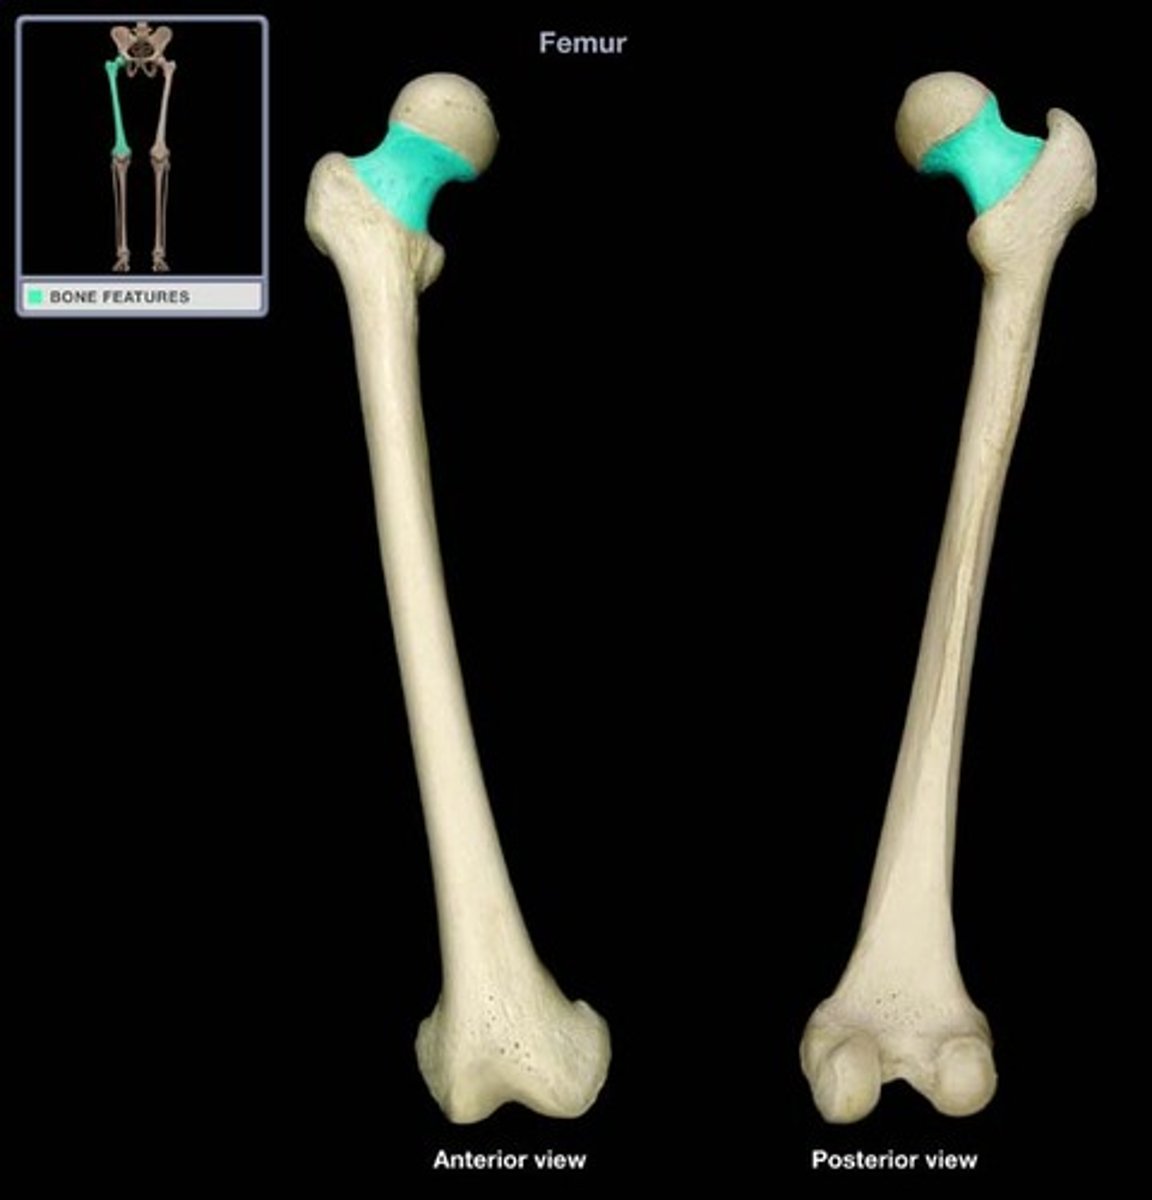

Neck of Femur